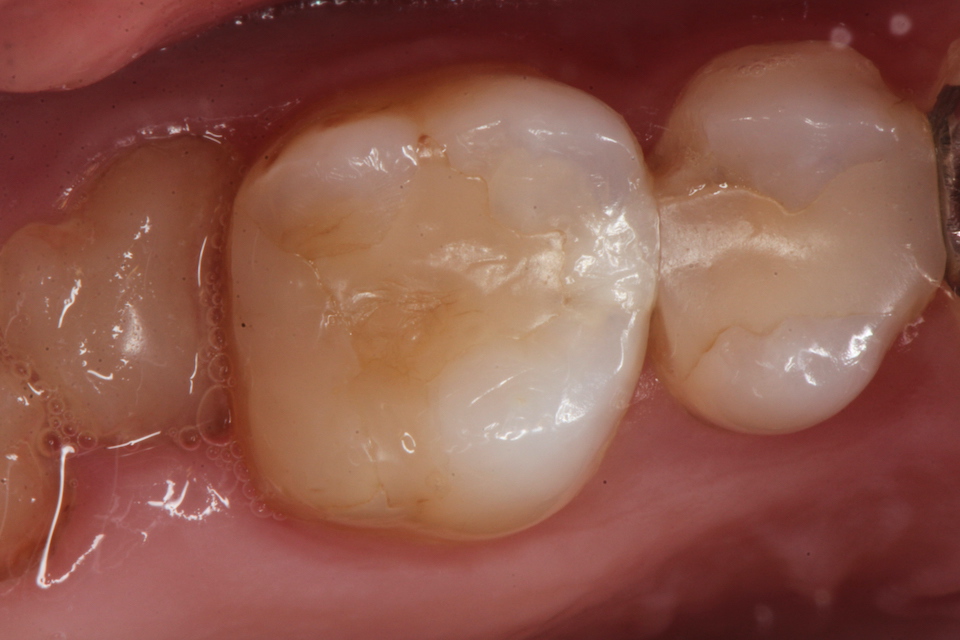

下顎7番の頬側歯茎部カリエスの原因 2025.06.04